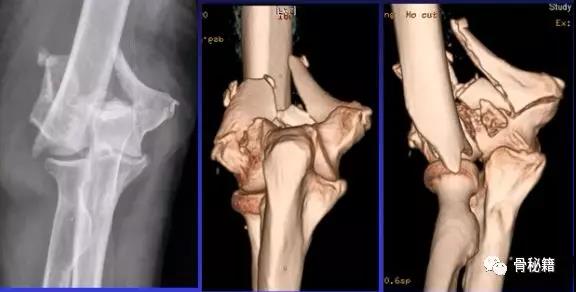

详细的术前评估

X线、CT、神经、等等

充分的的骨折显露手术入路(略)